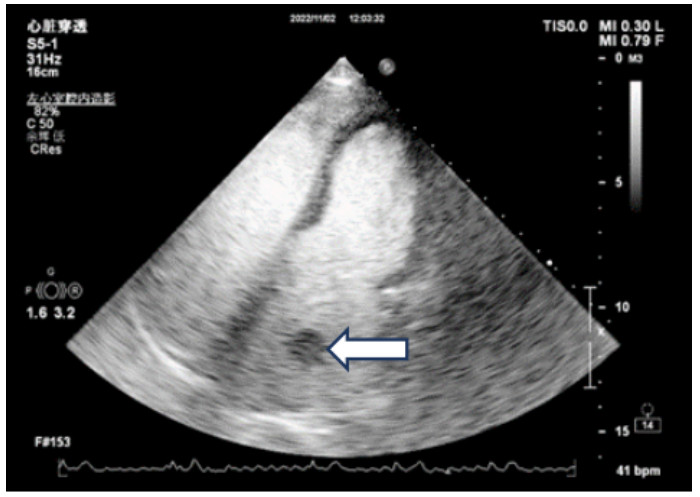

辅助检查:常规心电图示心房颤动。床旁经胸超声心动图示:原左房血栓影未显示(见图 3)。

| 注:左房内团块样回声影未见显示 图 3 患者本次入院当天常规经胸腔超声心动图 |